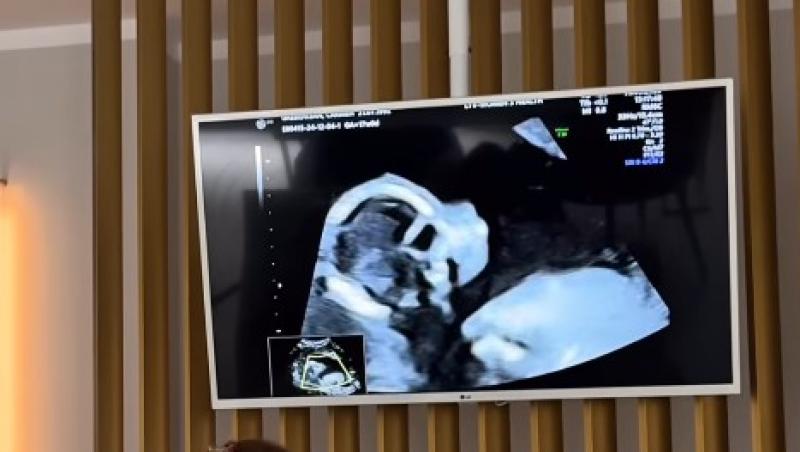

După o perioadă mai dificilă, marcată de un divorț, Carmen Grebenișan a reușit să se vindece și și-a găsit fericirea în brațele noului iubit. În urmă cu puțin timp, ea a postat pe rețelele de socializare primele imagini cu ecografia bebelușului.

Primele imagini cu bebelușul lui Carmen Grebenișan

Nașterea este așteptată în luna septembrie, iar viitorii părinți numără cu nerăbdare lunile rămase până când își vor ține copilul în brațe. Deși nu au dezvăluit încă sexul bebelușului, cei doi urmează să afle în curând și să aleagă și numele potrivit. Până atunci, influencerița le-a arătat urmăritorilor mai multe imagini cu ecografia bebeșului.

Carmen Grebenișan a împărtășit vestea sarcinii într-un mod spectaculos, printr-un videoclip postat pe rețelele de socializare, care surprindea o serie de momente din Miami, unde a inclus și imagini cu ecografia.